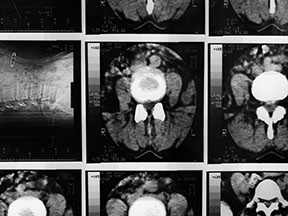

It is crucial to correctly identify the causes of pain to succesfully manage pain. ALLEGIANT utilizes the latest technological advances in diagnostic imaging and protocols.